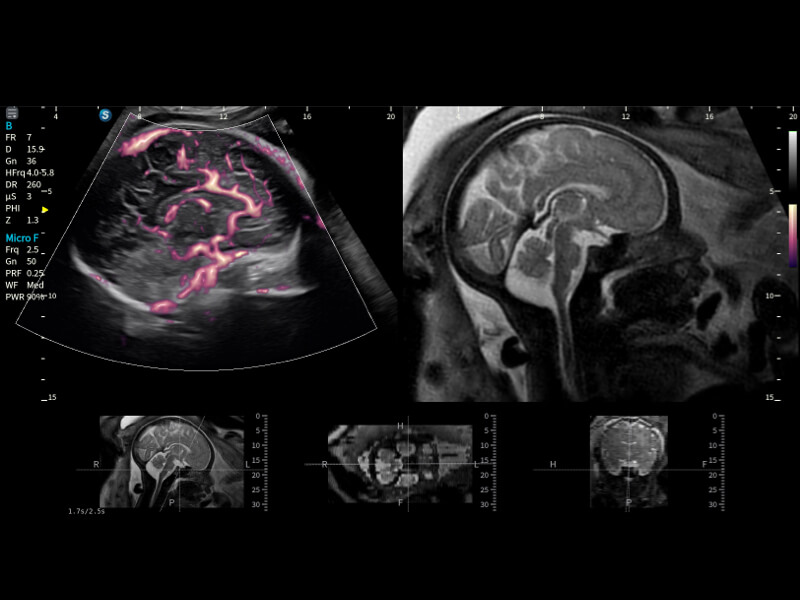

作為開立醫(yī)療全新打造的超高端旗艦超聲產(chǎn)品,從探頭抬起喚醒開啟掃查到多維探頭發(fā)射接收,通過先進(jìn)的場(chǎng)成像發(fā)射、自適應(yīng)聚合重建等技術(shù),基于RF Data原始射頻數(shù)據(jù)在圖像生成、高端功能等方面實(shí)現(xiàn)突破,為婦產(chǎn)科、兒科提供全方位臨床解決方案。

夢(mèng)溪?P80以“關(guān)愛女性”為基石,提供全方位的解決方案,量身定制以滿足女性的健康需求,涵蓋婦科、生殖健康檢查、產(chǎn)前篩查及產(chǎn)后康復(fù)等領(lǐng)域。